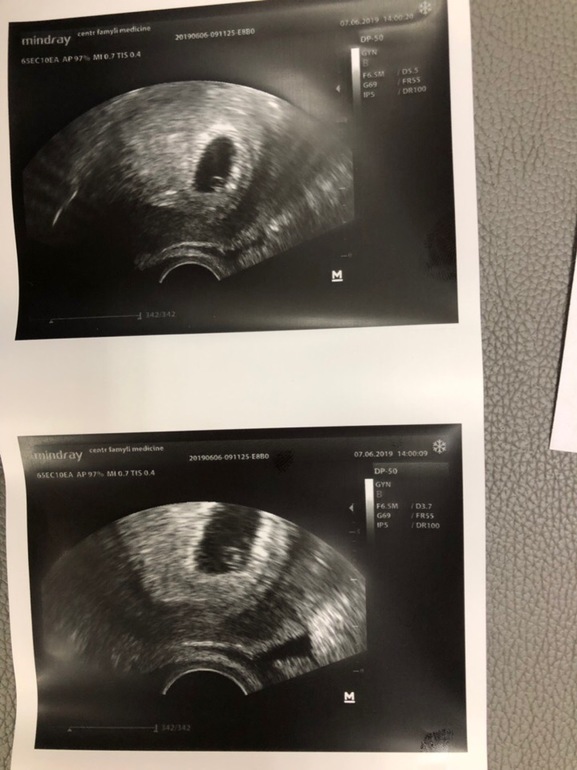

Первое УЗИ

Я БЕРЕМЕННА !Ура))) Дождалась я таки УЗИ. Лялечка одна)))) И сердечко бьется, девочки, это такой кайф, улыбаюсь до сих пор))) Все у нас очень хорошо, никаких отслоек, все соответствует сроку.